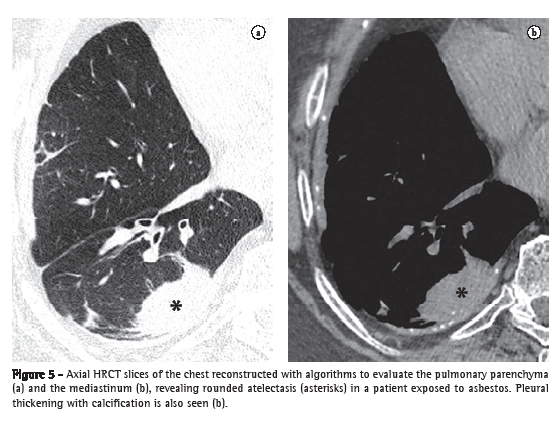

Rounded atelectasis (atelectasia redonda)

Rounded atelectasis is a type of oval-shape atelectasis caused by the adherence of the adjacent lung parenchyma to the area of pleural thickening, for example, in cases of asbestos-related pleural disease or empyema resolution.(15) It manifests as a rounded focal opacity to which bronchovascular structures converge (comet tail artifact) with a pleural base near the area of pleural thickening (Figure 5).(16,17) It presents homogeneous enhancement when iodinated contrast material is used.